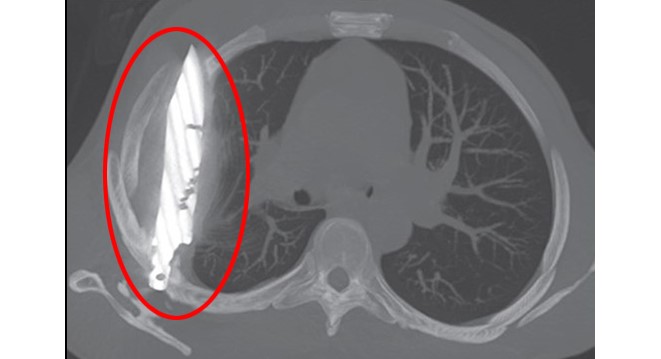

Röntgen sonucunda, adamın göğsünde 8 yıldır saplı duran bir bıçak olduğu ortaya çıktı. Hasta, yıllar önce yaşadığı kavgada yaralandığını ve o günden beri sağlık sorunu yaşamadığını belirtti. Vietnam'da ise bir başka şaşırtıcı olay yaşandı.

Tanzanya'da 44 yaşındaki bir adam, sağ memesinin altından iltihap akması şikâyetiyle hastaneye gitti. Doktorlar ilk muayenede herhangi bir ağrı, nefes darlığı, öksürük ya da ateş bulgusuna rastlamadı. Ancak yapılan röntgen, herkesin ağzını açık bıraktı: Adamın göğsünde tam sekiz yıldır saplı duran bir bıçak vardı.Hasta, yıllar önce yaşadığı şiddetli bir kavga sırasında yüzünden, sırtından, göğsünden ve karnından yaralandığını, o zaman tedavi gördüğünü söyledi. O günden beri ciddi bir sağlık sorunu yaşamamıştı. Fakat son günlerde fark ettiği iltihap nedeniyle doktora başvurunca, yıllardır göğsünde "unutulmuş" bıçak ortaya çıktı.

Bıçak, sağ kürek kemiğinden girip hayati organlara zarar vermeden göğüste kalmıştı. Ameliyatla çıkarılan bıçakla birlikte ölü doku temizlendi. Hasta yoğun bakımda bir gün, normal serviste ise 10 gün kaldı. Doktorlar, takip kontrollerinde hastanın tamamen iyileştiğini duyurdu.Vietnam'da ise akıllara durgunluk veren başka bir olay yaşandı.Hanoi'de bir adam, makatından giren 66 santimetrelik yılan balığının bağırsak duvarını kemirmeye başlamasıyla dayanılmaz ağrılar yaşadı. Çekilen röntgende balığın bağırsaktan çıkmaya çalıştığı görüldü.Doktorlar önce balığı özel bir cihazla çıkarmaya çalıştı, ancak önünde tıkalı bir limon buldular. Ameliyatla karnı açılan adamdan balık pense yardımıyla çıkarıldı. Ardından limon da anüsten geri itilerek çıkarıldı. Bağırsaktaki delik dikildi ve sızan dışkı temizlendi.